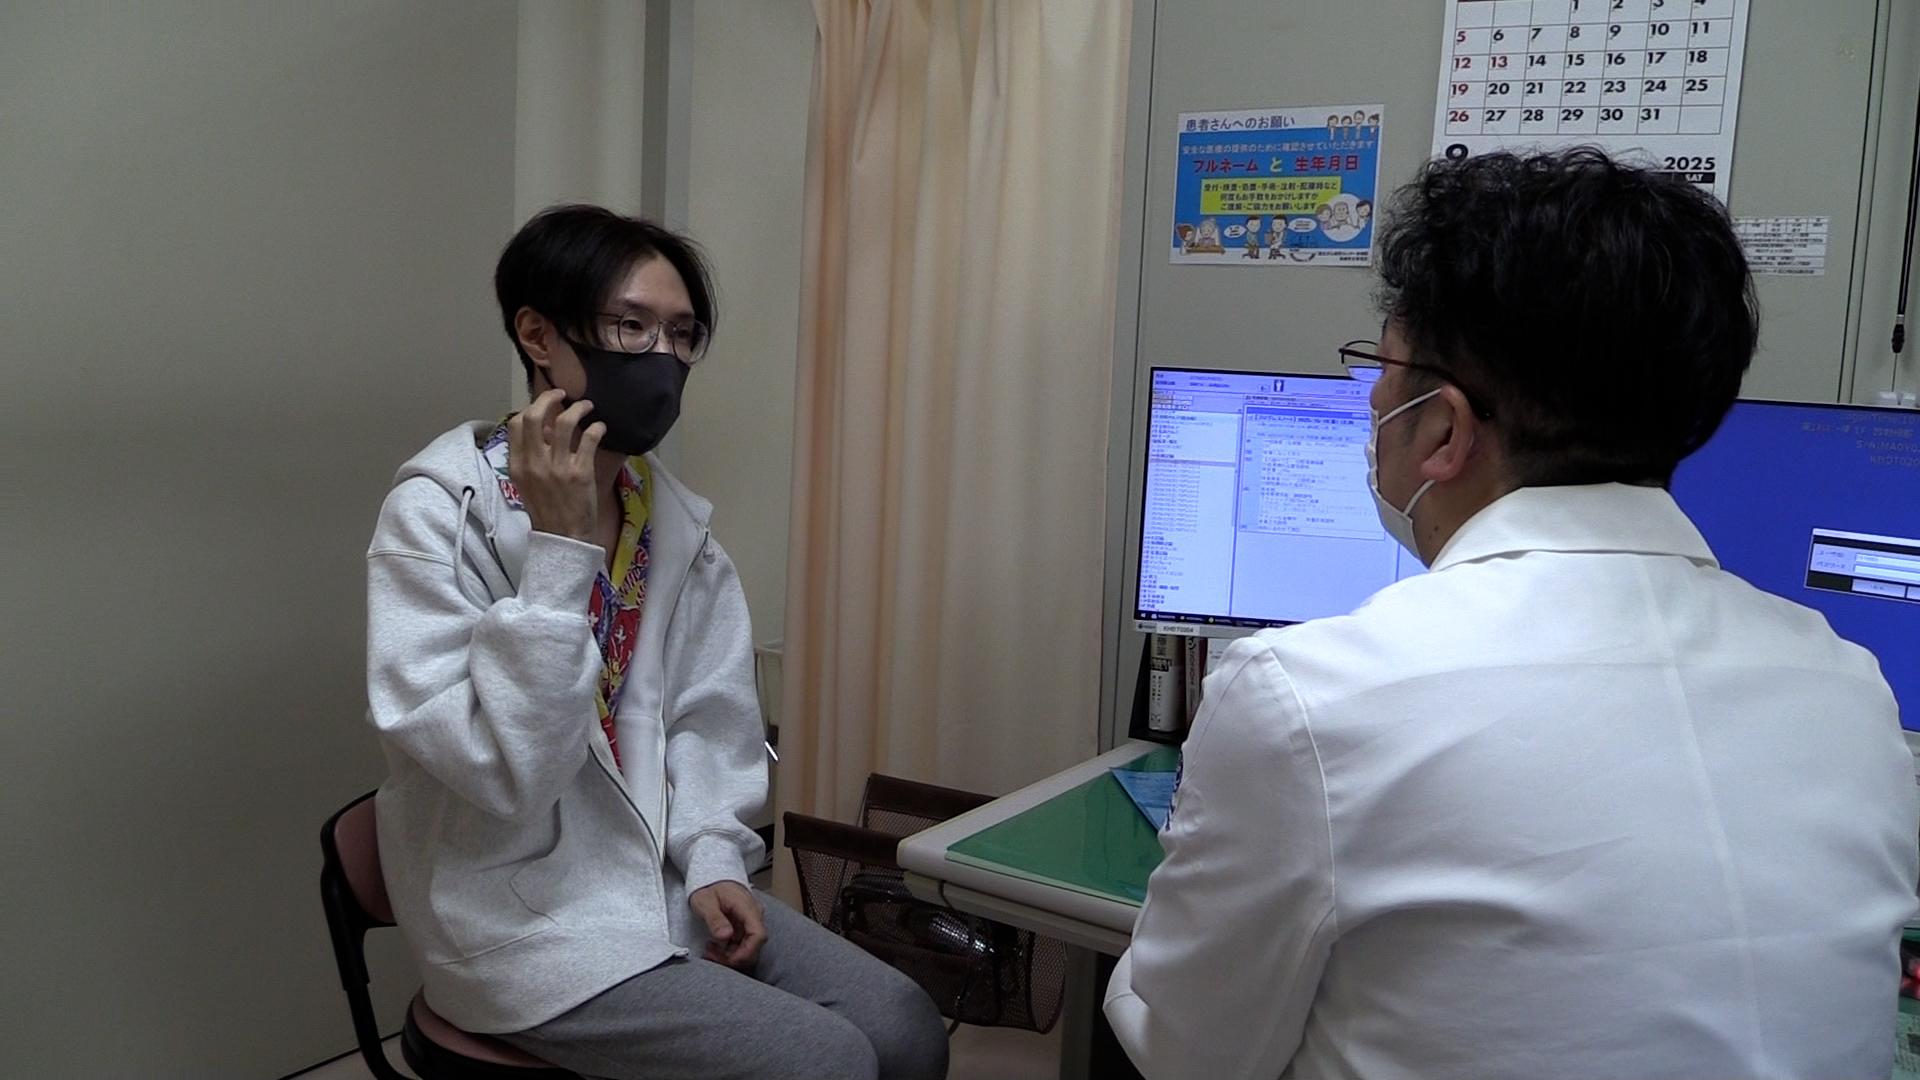

2人に1人が、癌になる時代。外科手術や薬物療法と並ぶ“癌治療の3本柱”の1つが、放射線治療だ。進化する癌の高精度放射線治療の最前線を取材。

2人に1人が、癌になる時代。外科手術や薬物療法と並ぶ“癌治療の3本柱”の1つが、放射線治療だ。「切らずに治せる治療」として身体への負担も少なく、仕事がある“現役世代”の患者が働きながら治療を受けられるメリットがあり、国内で新たに放射線治療を受ける癌患者は年間約23万人に増加している。

その放射線治療は、AIの進化などによる技術革新で、今後さらに治療の精度が上がることが期待されている。しかし、国内メーカーは装置の製造から相次ぎ撤退し、医療現場では海外メーカー製がシェアをほぼ独占する状態になっていた。ガイアは、進化する癌の高精度放射線治療の最前線を取材。これまでにない最新鋭の性能を武器に“悲願の国産装置”を開発した「日立ハイテク」と医師たちの挑戦を追う。